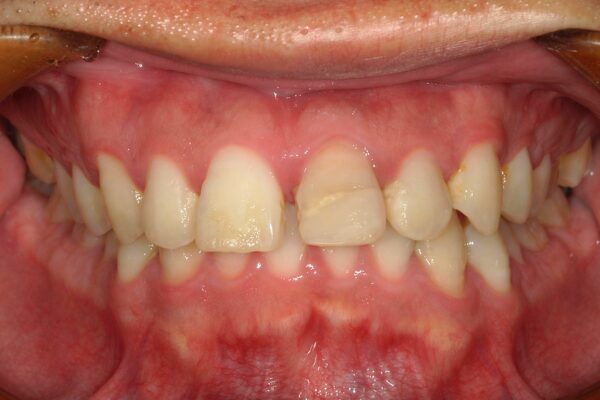

歯並びやお口のお悩み、

何でもご相談ください